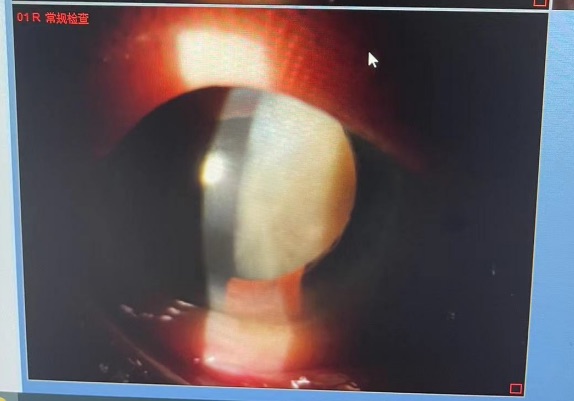

据上海医大医院眼科主任医师陈超丽介绍:裂隙灯下,彭爷爷的晶状体呈黑色,视力近乎失明。临床上最常用晶状体核硬度分级标准将核硬度分为五级——I度:透明,无核,软性;Ⅱ度:核呈黄白色或黄色,软核;Ⅲ度:核呈深黄色,中等硬度核;Ⅳ度:核呈棕色或琥珀色,硬核;V度:核呈棕褐色或黑色,极硬核。彭爷爷的白内障属于临床少见的V度,属于名副其实的极“硬核”白内障。只有通过手术换上人工晶体才能解决其眼部问题。